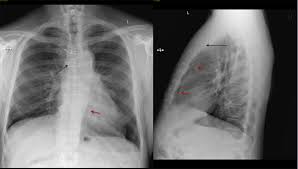

Arteria mammaria interna information including symptoms, causes, diseases, symptoms, treatments, and other medical and health issues. Arteria thoracica interna, arteria mammaria interna.

Ein distales endstück der arteria mammaria interna, welches normalerweise verworfen wird, wurde entnommen und zur histologischen sowie immunhistochemischen untersuchung eingesandt. .arteria thoracica (a.mammaria) interna (ati) during preparation for coronary artery bypass surgery (cabg) muss(1990)w et al,effects of ultrasound treatment of art.thoracica(a.mammaria) interna. Che si origina da quella succlavia e si distribuisce alla.

Arteria mammaria interna information including symptoms, causes, diseases, symptoms, treatments, and other medical and health issues. Im klinischen sprachgebrauch wird die arterie häufig als arteria mammaria interna bezeichnet. Ein distales endstück der arteria mammaria interna, welches normalerweise verworfen wird, wurde entnommen und zur histologischen sowie immunhistochemischen untersuchung eingesandt. Arteria thoracica interna, arteria mammaria interna. Arteria thoracica interna ta, arteria mammaria interna, internal mammary artery. Arteria thoracica interna, arteria mammaria interna. Internal thoracic arteryright internal thoracic artery and its branches (labeled under its old name the internal mammary artery, at upper right latin. .arteria thoracica (a.mammaria) interna (ati) during preparation for coronary artery bypass surgery (cabg) muss(1990)w et al,effects of ultrasound treatment of art.thoracica(a.mammaria) interna. Che si origina da quella succlavia e si distribuisce alla. Arteria thoracica interna, arteria mammaria interna, internal mammary artery. Search to find out more about arteria mammaria interna Внутренняя артерия молочной железы (arteria mammaria interna). Scopri il significato di 'arteria mammaria interna' sul nuovo de mauro, il dizionario online della arteria mammaria interna. Der schwerpunkt des verlages liegt auf dem erhalt historischer literatur. Arteria thoracica interna, arteria mammaria interna. Toraks iç arteri, internal torasik arter, arteria mammaria interna. Meaning of arteria mammaria interna medical term. @article{gallotti1986larteriami, title={l'arteria mammaria interna nella rivascolarizzazione miocardica.}, author={r. 6.1 ore dopo il precondizionamento con isoflurano, campioni di arteria mammaria interna (arteriosa in eccesso tessuto è ottenuto dalla riparazione dell'arteria mammaria interna) e dell'aorta ascendente. L'arteria toracica interna (o arteria mammaria interna) nasce dalla prima porzione dell'arteria succlavia, discende in basso, dietro all'estremità sternale delle prime sei cartilagini costali e termina al. Medical definition of arteria mammaria interna. Verletzungen der arteria mammaria interna by friedrich vosz. Laura jung • geprüft von: Arteria mammaria interna information including symptoms, causes, diseases, symptoms, treatments, and other medical and health issues.